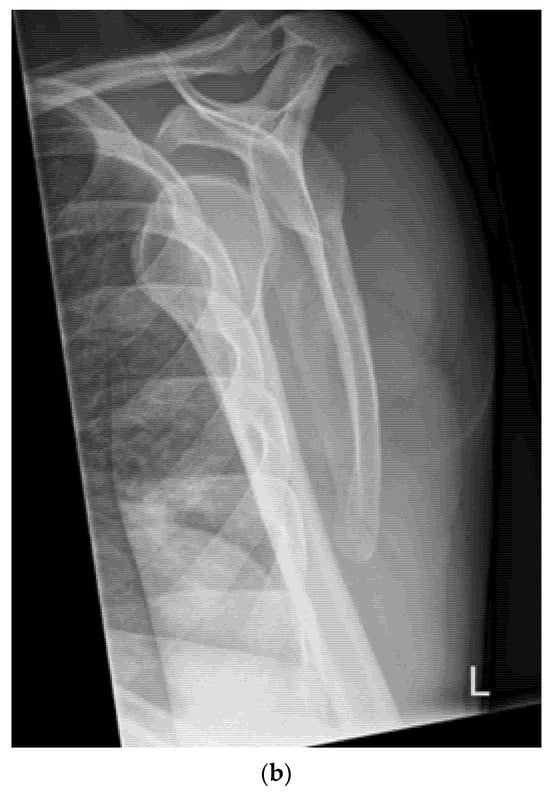

- Quick exclusion of fractures in shoulder dislocations for timely reduction (Figure 13).

- Recommendation 6: Ultrasound should be integrated into the assessment and management of shoulder injuries, including proximal humerus fractures, shoulder dislocations, and post-relocation maneuvers, both prehospitally, in emergency departments, and other acute care settings.

- Example: Suspected left shoulder dislocation

- Integrated into the assessment and management of shoulder injuries, including proximal humerus fracture, shoulder dislocation, and post-relocation maneuver, both pre-hospital and in emergency department settings.